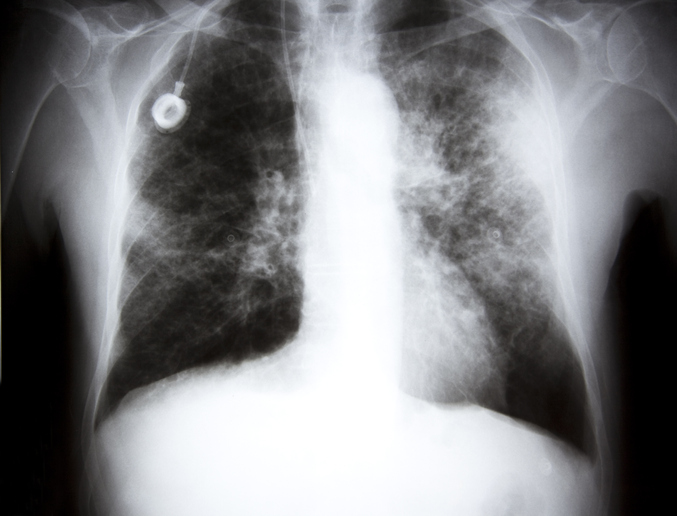

Chest X Ray Diagnosing Lung Cancer Cancer Research Uk